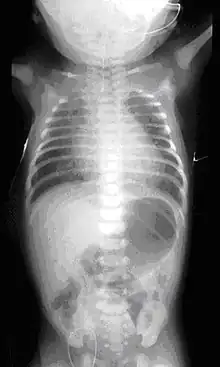

Plain x-ray with contrast in the upper esophagus above the atresia.

On plain X-ray, a feeding tube will not be seen pass through the esophagus and remain coiled in the upper oesophageal pouch.[8]